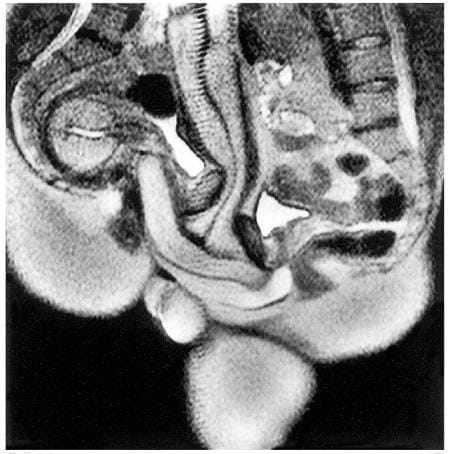

20年前、オランダのある研究チームがちょっと怪しげなタイトルの論文を発表した。「性行時、そして女性の性的興奮時における男女の性器の磁気共鳴映像(MRI)」----。これはMRI装置の中でのセックスに関する初の記録であるとともに、世界トップクラスの歴史と権威をもつ医学誌ブリティッシュ・メディカル・ジャーナルBMIのあまたの論文の中で最もダウンロード数が多い論文の1つとなっている。それも、記念碑的な論文だけが選ばれて掲載されるクリスマス号を飾ったのだ。

研究チームの狙いは、MRI装置の中でセックスしている最中の人の性器を撮影できるかどうか、そして当時のセックスに関する常識が正しいかどうか確かめることにあった。

MRI装置が置かれた部屋は研究チームのいる制御室の隣にあり、窓のカーテンは閉じられていた。研究チームはまず、女性たちに仰向けに寝てもらい、下腹部を撮影した。次に男性たちに部屋に入ってもらい、正常位でセックスをしてもらって画像を撮影。そのあと、男性は退室し、女性たちは自分で自分を刺激して達するよう指示される。いよいよというタイミングで女性から研究チームに合図が送られて撮影が行われ、それから20分後の画像も撮影して実験は終了した。

画像の分析から、正常位だとペニスがブーメランのような形になることや、女性が興奮すると子宮が持ち上がったようになり、膣壁が長く伸びることが分かったという。